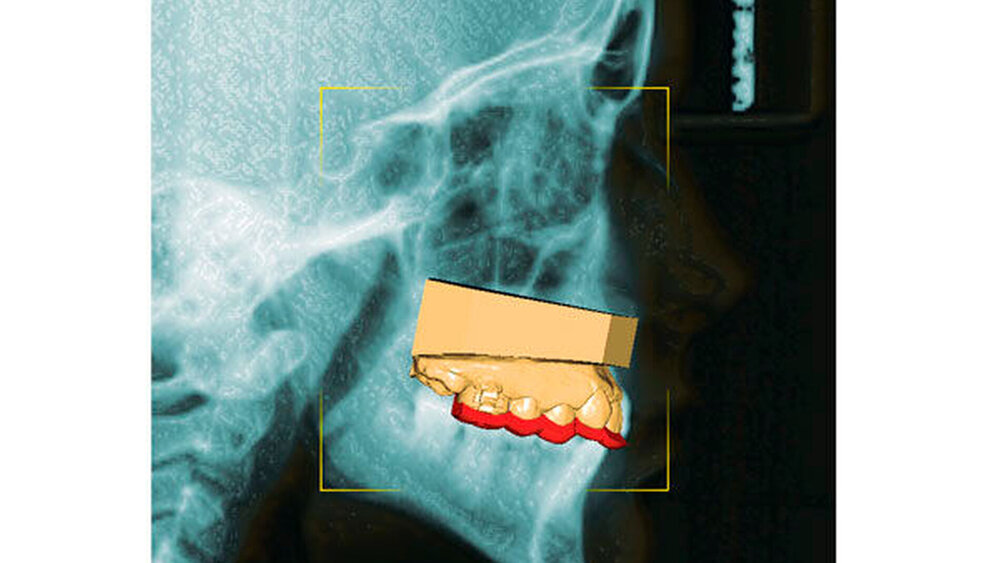

Wie beim Einbringen von Zahnimplantaten schaffen die computergestützte Planung und die Verwendung von Schablonen auch bei der Insertion von Mini-Implantaten mehr Sicherheit für den Behandlungserfolg. Für die zunächst virtuelle Insertion werden ein Abdruck oder ein Scan sowie ein Röntgenbild (FRS oder DVT) überlagert [De Gabriele, 2017] (Abbildungen 1 und 2, Easy Driver Software, Labor Uniontech, Parma/IT). Während in einem normalen Fall das FRS ausreicht, ist bei schwierigen Situationen (zum Beispiel LKG-Spalte, palatinal verlagerte Eckzähne) sicherlich die Anfertigung eines DVTs empfehlenswert. Basierend auf der computergestützten Planung wird eine Insertionsschablone per Rapid-Prototyping-Verfahren (RKS Labor, Rastede/D, Abbildung 3) zusammen mit dem gewünschten kieferorthopädischen Gerät im zahntechnischen Labor hergestellt.

Das Prinzip einer CAD/CAM-gesteuerten Insertion wird anhand einer zehnjährigen Patientin mit einem Platzmangel für die oberen Eckzähne dargestellt (Abbildungen 4a, 4b). Die Behandlung begann mit dem Anpassen von Molarenbändern und einem Silikon-Abdruck des Oberkiefers, der mit dem FRS an das zahntechnische Labor gesendet wurde und dort mit dem FRS der Patientin überlagert wurde. So konnten geeignete Insertionsstellen virtuell geplant werden (Abbildungen 1, 2a, 2b). Nach Rücksprache mit dem Behandler bezüglich der Mini-Implantatpositionen erfolgte die Herstellung der Insertionsschablone (Abbildung 3). Parallel dazu wurde auch der Beneslider [Wilmes, 2010] hergestellt, der zusammen mit der Insertionsschablone geliefert wurde (Abbildung 5). Mithilfe der Insertionsschablone konnten die Mini-Implantate und der Beneslider im selben Termin eingesetzt werden (Abbildungen 6, 7a, 7b). Nach 10 Monaten Distalisierung waren die Molaren in der Zielposition und es war ausreichend Platz für die Eckzähne vorhanden (Abbildungen 8a, 8b), so dass Brackets für die zweite Phase der Behandlung eingesetzt werden konnten. Die Multibracket-Apparatur (Abbildung 9) konnte nach 12 Monaten entfernt werden (Abbildungen 10, 11).